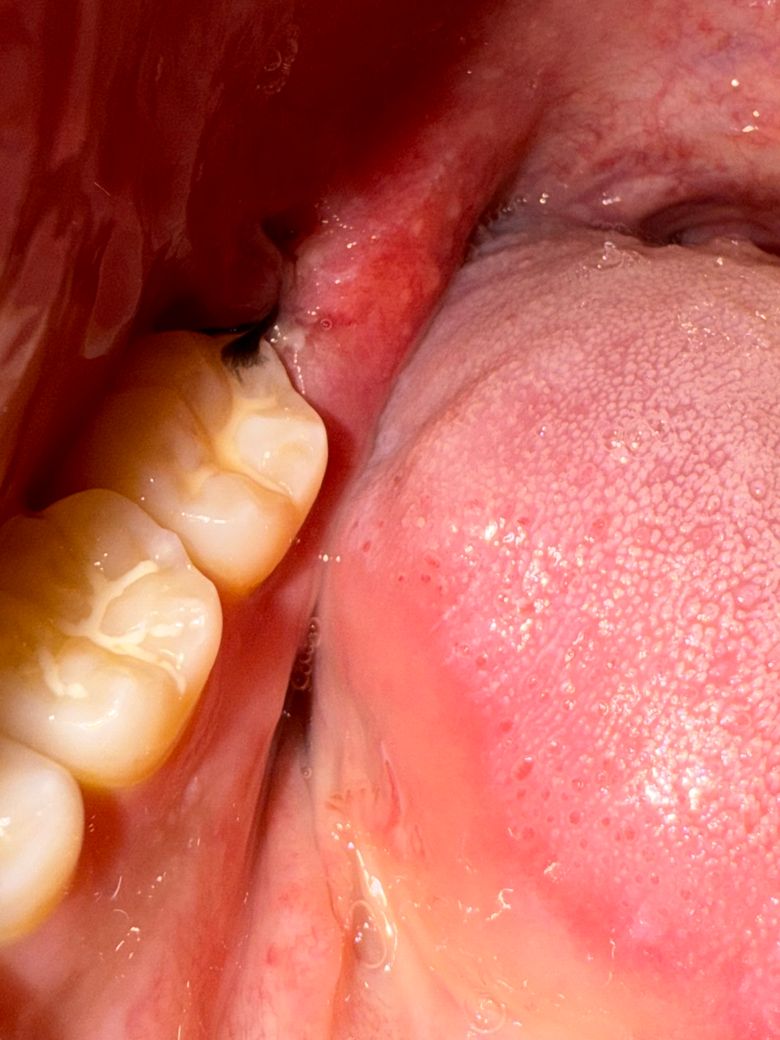

흰색으로 동그라미 친 부분에 구멍 같은게 보이고 실밥도 하나가 풀렸습니다… 얼굴 붓기는 더 붓고 통증은 아주 실짝 있네요. 혹시 드라이소캣이나 문제가 있는거일까요?..(원본 사진도 첨부합니다!)

사진상 잇몸은 어느정도 잘 낫고 있습니다 너무 걱정하지 마시고 발치 후 주의사항 잘 지키시기 바랍니다

사진으로 봤을 경우에는 발치한 부위가 잘 아물고 있는 것으로 보입니다. 너무 걱정하지 않으셔도 될 것으로 생각됩니다. 사랑니를 발치한 부위는 자극되지 않는 것이 좋습니다. 자극이 된다면 출혈이 되고 치유가 늦어질 수 있기 때문입니다.

사랑니 발치 후 3일차인데 괜찮은건가요??-> 문제는 없어보이고 잘 낫고 있는 것 같습니다.

아직 잇몸상처나 붓기가 다 가라 앉지 않아서 그러는거니 너무 걱정하지 않으셔도 될것같습니다.